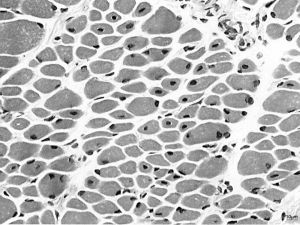

利用肌肉切片的病理分析,可診斷患者是否罹患此疾病。患者的肌肉切片中可發現細胞核聚集於肌肉纖維中,而非散布於肌肉纖維四周。另外,利用免疫染色分析法可發現肌肉纖維中,有如同胎兒肌肉的特異蛋白質(如desmin及fetalmyosin等)。肌肉切片雖可診斷出此疾病,但無法達到分型的目的,若要進行分型,必須仰賴基因診斷。遺憾的是,截至21世紀初只有X染色體遺傳型確認為是位於Xq28的MTM1基因發生變異所致,其他兩型之致病基因未明。